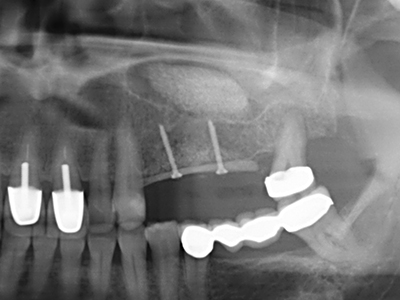

Fig. 11: The postoperative panoramic image shows the vertical augmentation and sinus floor elevation.

Fig. 13: Adequate irrigation with the 4-mm residual bone width is essential for this 52-year-old patient during the bone splitting.

Fig. 15: The one-year follow-up x-ray examination shows stable conditions at the bone level.